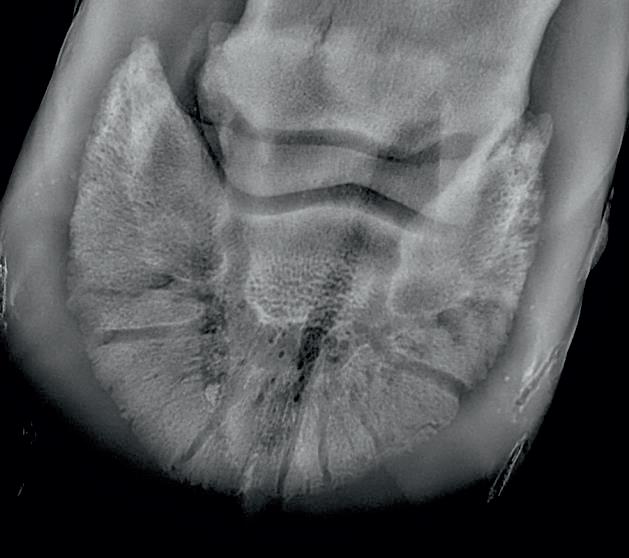

Here is a veterinary radiographic report on a horse with a fracture evident on the medial toe and after treatment and feeding Bone Gold during this period. More information on these products can be found at www.vetgold.com.au

VETERINARY RADIOGRAPHIC REPORT

DATES OF EXAMINATION: 26TH AUG, 21ST OCT 21 & 17TH NOV '21

PLACE: XXXXXXXXXX FARM

DATES OF EXAMINATION: 26TH AUG, 21ST OCT 21 & 17TH NOV ‘21

XXXXXXX's left and right front feet were radiographed on 26th Aug, 21st Oct (8 weeks) and again on the 17th Nov '21(12 weeks).

XXXXXXX’s left and right front feet were radiographed on 26th Aug, 21st Oct (8 weeks) and again on the 17th Nov ‘21(12 weeks).

26.08.21: Right Front: Large P3 solar margin fracture evident on medial toe 32.6mm x 4.1mm with approximately 1.4mm separation from parent bone as below left image.

21.10.21: Right Front: Fine residual 4.2mm fracture still evident, approximately 90% resolution

17.11.21: Right Front: Fracture fully resolved

26TH AUG 21

21ST OCT 21

Radiographic results as of the 17th Nov '21 show total resolution of the original fracture.

XXXXXXX was reshod today utilising off an alloy shoe with a toe clip - inner circumference seated out to avoid any sole pressure. The horse can return to training.

Solar margin Type IV fractures of this magnitude have well-documented internationally published healing rates of 7 - 12 months. Full resolution of these fractures is rare as most often the fracture fragments are resorbed. Full resolution in a 3 month period was not anticipated.

The horse was on Bone Gold 3 x scoops fed once per day for this period.